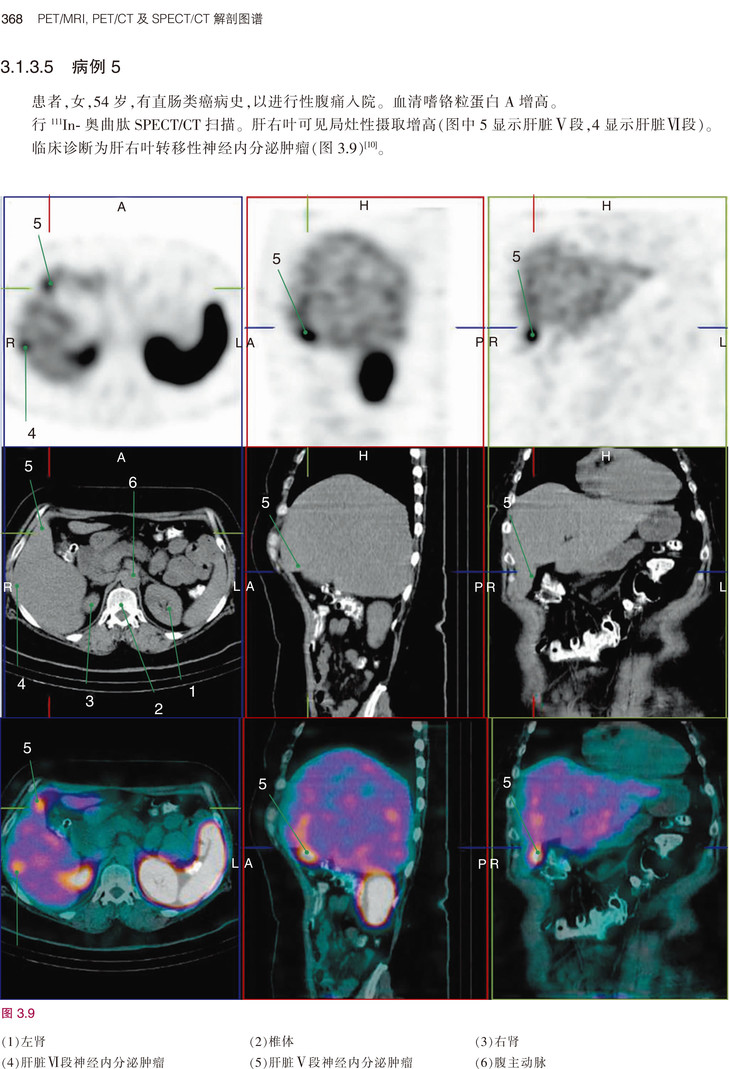

《PET/MRI, PET/CT及SPECT/CT解剖图谱》是目前融合医学影像的经典著作,书中既讲解了基础解剖内容,又有丰富的病例介绍。全书共3章内容,分别为PET/MRI解剖图谱、PET/CT解剖图谱和SPECT/CT解剖图谱。第1章PET/MRI解剖图谱按照大脑、头颈部、胸部、腹部、盆腔、肌肉骨骼系统进行描述。第2章PET/CT解剖图谱按照FDG和非-FDG进行分类描述。第3章则描述了肿瘤、骨和其他病变的SPECT/CT表现。本书编者临床经验丰富、理论基础扎实、科研能力出众,以“融合图像”作为突出特色,荟萃了当今最为先进的PET/CT、PET/MRI及SPECT/CT技术,有助于提升国内从业人员的专业素养、优化诊断思路,进而更好地服务于患者。